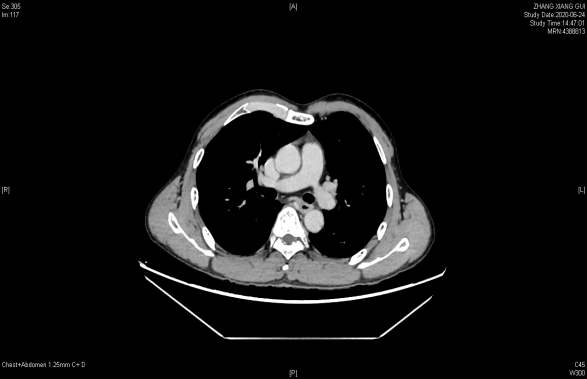

联合治疗2周后胸部增强CT:食管中段管壁增厚,增强扫描呈较明显不均匀强化,较前好转,胸廓入口水平气管右侧见肿大淋巴结,明显不均匀强化,较前减小。

2020年6月24日 联合治疗2周期后胃镜(上)和胸部增强CT(下)

患者经过2周期联合治疗后,于2020年6月24日胃镜及胸部增强CT提示食管下段病灶基本消失,身体状况良好,具备较好手术机会。